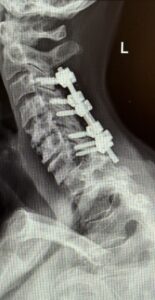

The patient is a 61-year-old female with a history of rheumatoid arthritis. She is 2-1/2-years status post C3-C7 laminectomy with posterior instrumentation and fusion. This procedure was performed to treat multilevel disc herniations with spinal cord compression following a motor vehicle accident.

Her rheumatologist ordered an x-ray which showed anterolisthesis of C7-T-1 with kyphosis and instability (Fig 1 right).